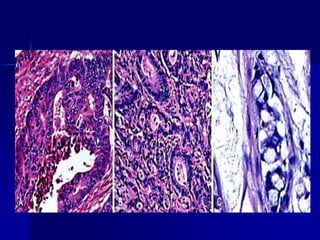

A. Hay un infiltrado linfoplasmocítico denso superficial en la lámina propia. B. Agregado linfoide; cuando está presente,

es altamente sugestivo de Helicobacter. C. Los neutrófilos se encuentran dispersos en el infiltrado de la lámina propia y

pueden penetrar el epitelio glandular. D. La tinción de Warthin- Starry resalta los pequeños organismos curvilíneos en la

superficie foveolar